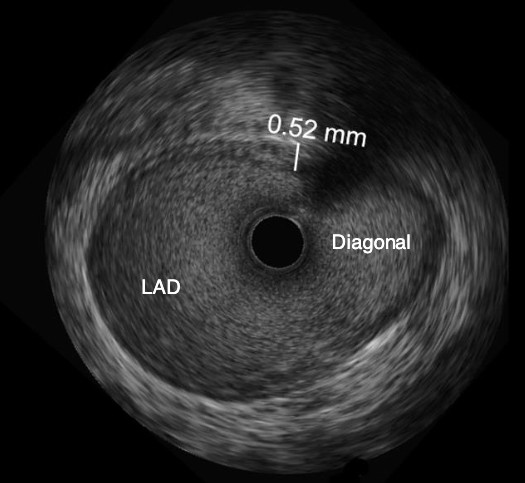

OPTICROSS HD Imaging Catheter vs. Competitor

High-Definition IVUS image quality helps physicians more accurately identify lesion length, assess plaque morphology, and determine the tools required for vessel prep. See how OPTICROSS HD’s 60 MHz images stack up against the competition.

OPTICROSS Imaging Catheter 40 MHz

IVUS image of inside a coronary vessel using the 40MHz Opticross catheter

Axial resolution: 38 µm

OPTICROSS HD Imaging Catheter 60MHz

IVUS image of inside a coronary vessel using the 60MHz Opticross catheter

Axial resolution: 22µm

Philips Volcano Eagle Eye Platinum Imaging Catheter 20MHz

IVUS image of inside a coronary vessel using the 20MHz Philips Volcano Eagle Eye Platinum catheter

Axial resolution: <170 µm

Philips Volcano Revolution Imaging Catheter 45MHz

IVUS image of inside a coronary vessel using the 45MHz Philips Volcano Revolution Platinum catheter

Axial resolution: 50 µm

OPTICROSS versus OPTICROSS HD images courtesy of Michael Kim, MD, FACC, FSCAI North Colorado Medical Center